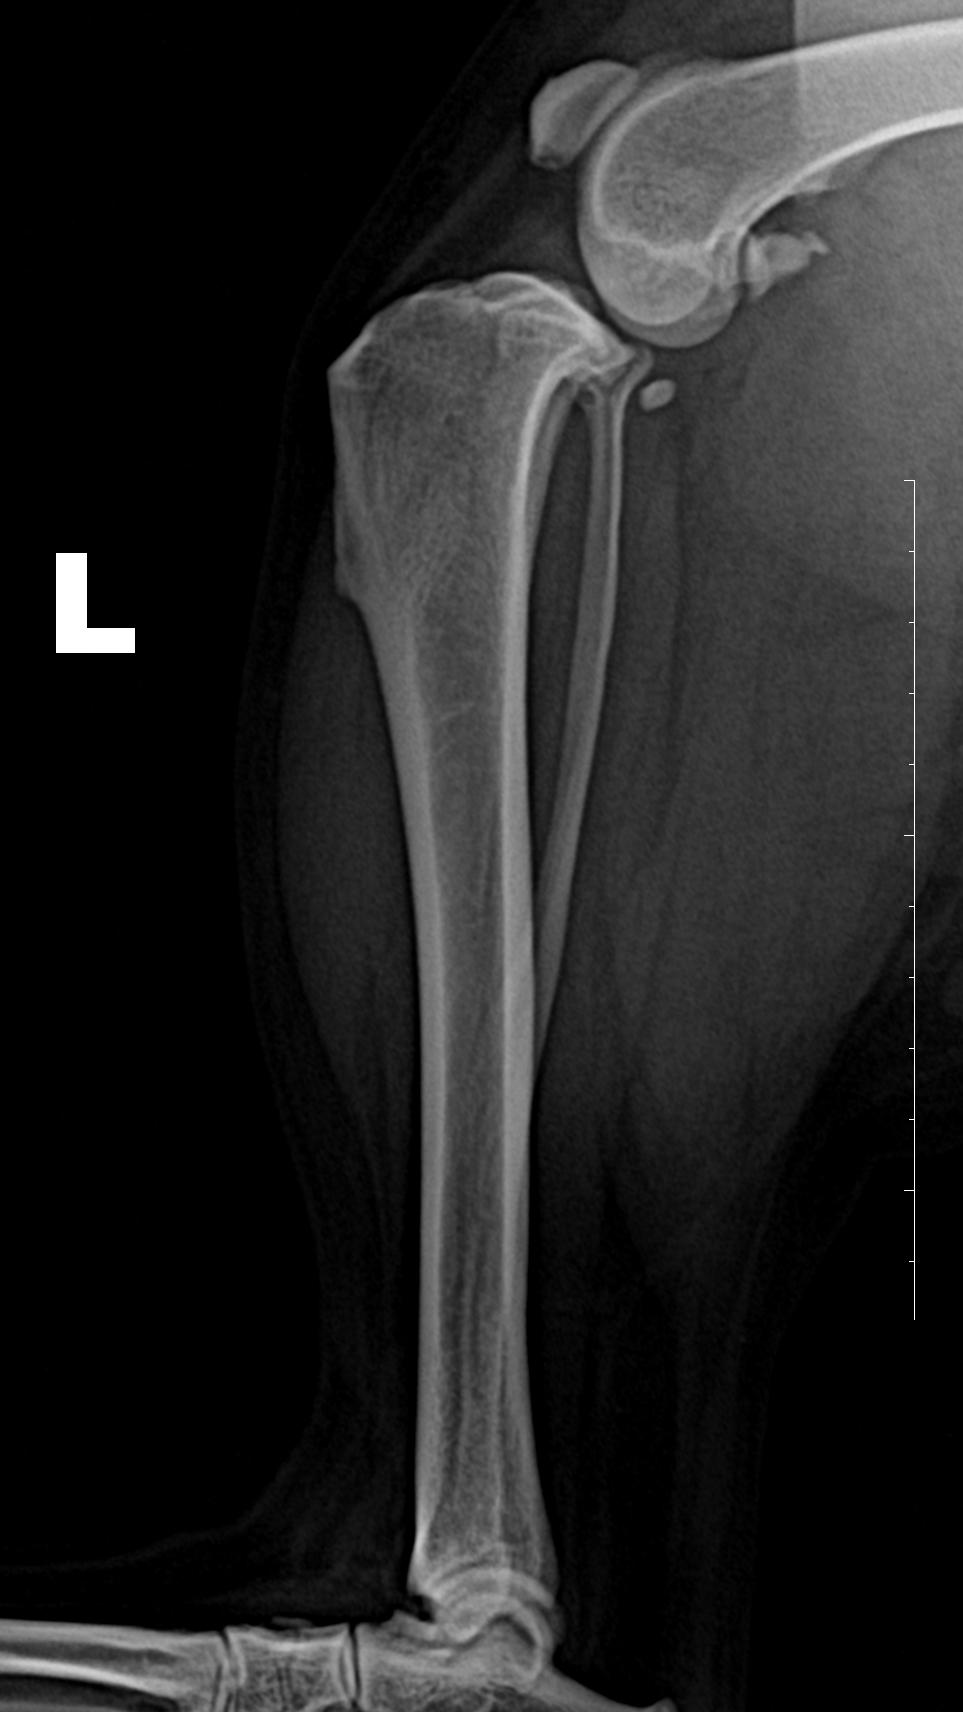

DR检查

右后肢股骨滑车脊的关节周围有新骨生成。

左、右后肢侧位 片 关节腔内软组织不透明度增加,膑下脂肪垫向前位移;

右后肢前后位↑

右后肢内外位↑

正位片可见关节内侧软组织不透明度增加;胫骨粗隆前移。